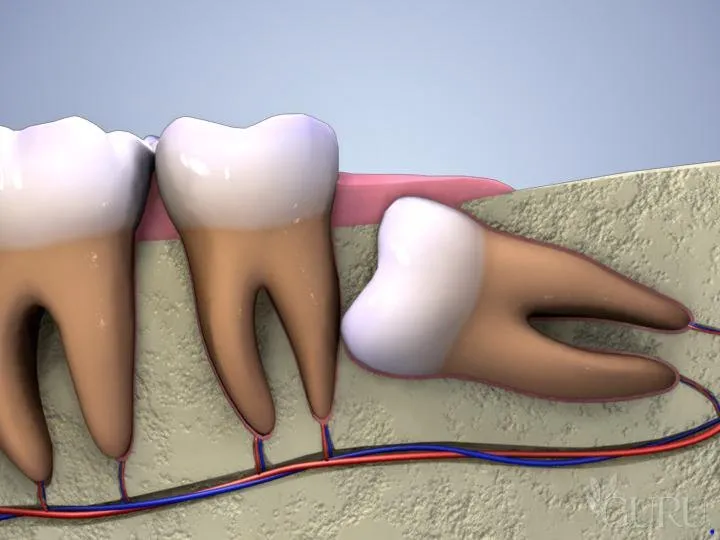

Răng khôn là chiếc răng cuối cùng mọc trên cung hàm của mỗi người. Chúng nằm ở vị trí trong cùng, sau răng số 7 (răng hàm lớn thứ hai).

- Cung hàm không đủ chỗ: Đây là nguyên nhân phổ biến nhất. Khi răng số 8 bắt đầu mọc, toàn bộ các răng khác trên cung hàm đã ổn định vị trí. Nếu xương hàm của bạn có kích thước nhỏ hoặc các răng khác quá lớn, không còn đủ khoảng trống, răng khôn buộc phải tìm đường mọc theo hướng bất thường, dẫn đến mọc nghiêng, mọc lệch hoặc mọc kẹt, mọc ngầm hoàn toàn dưới nướu và xương hàm.

- Xương hàm đã cứng: Ở độ tuổi 17-25, xương hàm đã phát triển hoàn chỉnh và trở nên đặc, cứng. Điều này khiến cho quá trình mọc của răng số 8 gặp nhiều khó khăn hơn so với các răng khác mọc ở giai đoạn trẻ em.

- Sự cản trở từ răng số 7: Răng 8 mọc ngầm thường gặp sự cản trở từ chân hoặc thân răng số 7 ở phía trước, khiến nó không thể trồi lên đúng vị trí thẳng đứng.